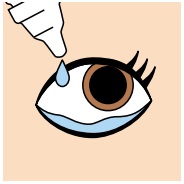

抗VEGF薬治療(硝子体内注射)の眼内注射をおこなう前後の注意点

抗VEGF治療薬を行う前の3日間、行ったあとの3日間は、感染予防のために抗菌点眼薬を患者様ご自身で点眼していただく必要があります。

抗VEGF治療薬を行う前の3日間、行ったあとの3日間は、感染予防のために抗菌点眼薬を患者様ご自身で点眼していただく必要があります。

注射の際には改めて消毒を行いますが、感染リスクをできる限りゼロに近づけるめ、必ず医師の指示通りに点眼を行ってください。